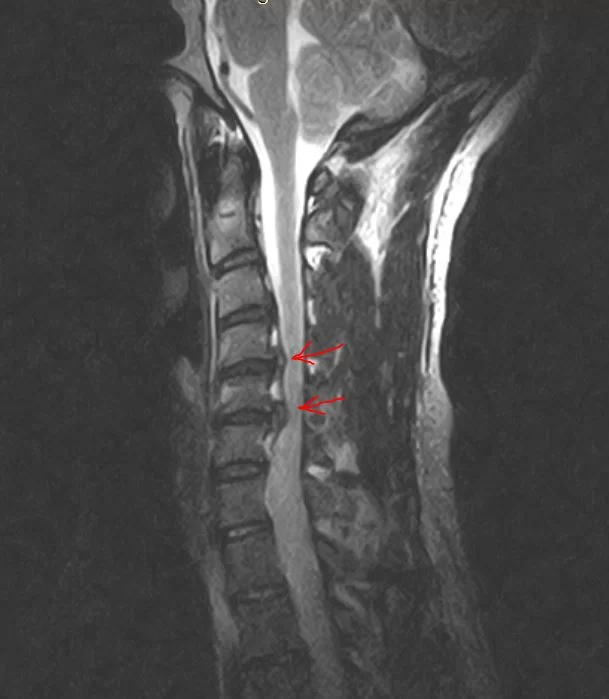

Η αυχενική δισκεκτομή είναι η χειρουργική επέμβαση κατά την οποία αφαιρείται ο σπασμένος ή εκφυλισμένος δίσκος ο οποίος πιέζει κάποιο νεύρο ή τον νωτιαίο μυελό (Εικόνα 1).

Ο εκφυλισμός του δίσκου και των σπονδύλων (οστεόφυτα) μπορεί να επηρεάσουν το διαθέσιμο χώρο για το νωτιαίο μυελό και τα νεύρα. Ως αποτέλεσμα, ο νωτιαίος μυελός και τα νεύρα ενδέχεται να συμπιεστούν ή και να τραυματιστούν.